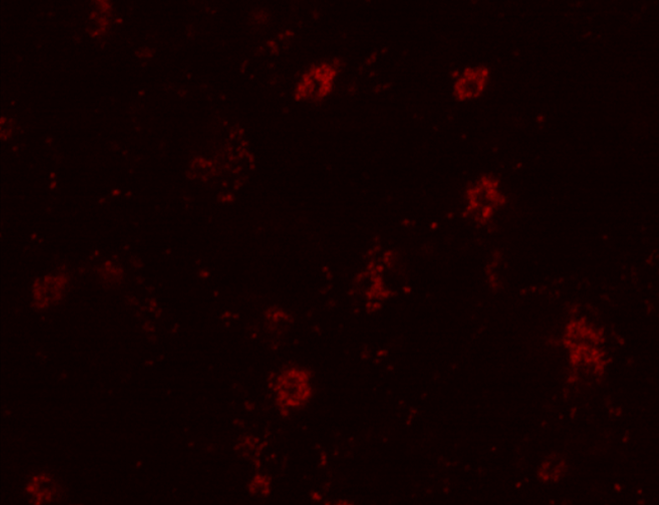

Чтобы доказать, что продукты окисления могут испускать свет в красном спектре после облучения, ученые сначала подвергали водные растворы белков и ДНК фотоокислению, после чего измеряли оптические свойства полученных образцов. Сигнал, исходящий от необлученных образцов, был почти незаметен, в то время как окисленные молекулы флуоресцировали в широком диапазоне длин волн возбуждения, включая красный свет.

На втором этапе исследования были изучены качественные характеристики флуоресценции продуктов окисления в кератиноцитах — клетках человеческой кожи. На них подавали ультрафиолетовое излучение с длиной волны 254 нанометра. Сразу после этого изменений не наблюдалось, однако интенсивность излучения увеличилась спустя 5-15 часов в зависимости от силы возбуждающего света. Кератиноциты были взяты для исследования, так как верхний слой кожного покрова состоит из них на 90%, и под воздействием ультрафиолетового излучения в коже образуется большое количество свободных радикалов, усиливающих процесс окисления. Флуоресценция клеток, в которых происходит окислительный стресс, может перекрывать фоновый сигнал биологических тканей.